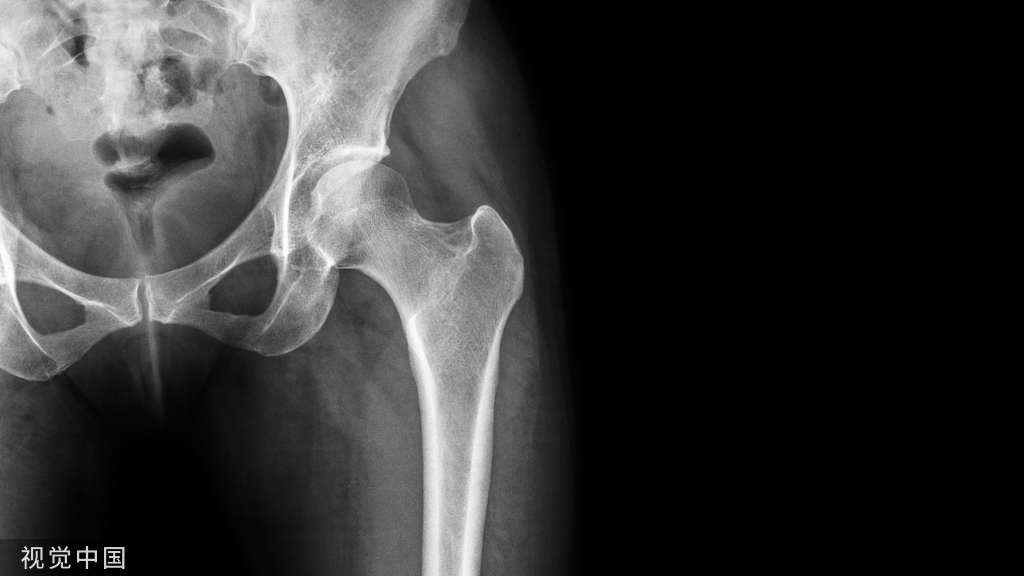

正常的髋关节:是球窝关节、股骨头嵌入骨盆的关节窝内(髋臼)

正常髋关节

髋关节 是人体最大的负重关节,它包括两个主要的部分:股骨近端的球形部分—股骨头被包容在骨盆上的髋臼内。有一条韧带—圆韧带链接着髋臼和股骨头,提供了关节的稳定。

股骨头和髋臼的骨质表面均覆盖着光滑的关节软骨,使它们之间的运动更加灵活。关节的表面有一层薄的、光滑的滑膜组织覆盖。在正常的髋关节中,滑膜组织可以分泌出少量的液体,这些液体对髋关节起到润滑作用以减少股骨头和髋臼之间的磨损。